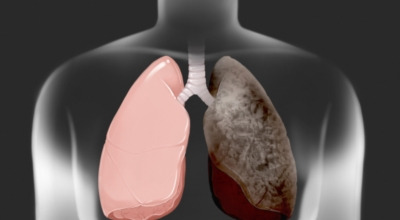

폐암 원인

폐암의 공통적인 위험 요소로 손꼽히는 이유 중 하나가 바로 흡연입니다. 흡연자는 비흡연자에 비해 폐암 발병 확률이 수십 배나 높다고 하며, 흡연을 해온 기간이 길수록 그 위험은 더욱 커집니다. 하지만 흡연자라 하더라도 금연을 하면 폐암 발병 확률이 빠르게 낮아진다고 하니, 폐암이 걱정되신다면 무엇보다 먼저 금연이 필수입니다.

간접흡연 외에도 공사장과 같은 환경에서 미세먼지나 석면, 비소, 라돈, 카드뮴 등 인체에 해로운 물질에 노출될 경우에도 폐암이 발생할 수 있다고 합니다. 또한 유전적인 요인으로도 폐암이 발병할 수 있는데요, 가족 중 폐암을 앓았던 분이 있다면 그렇지 않은 경우에 비해 약 2배 정도 폐암에 걸릴 확률이 높다고 해요. 이처럼 폐암은 본인도 모르는 사이에 발병할 수 있기 때문에, 평소 자신의 신체 상태를 자주 확인하고 이상 징후가 있을 때 조기에 발견하는 것이 무엇보다 현명합니다.